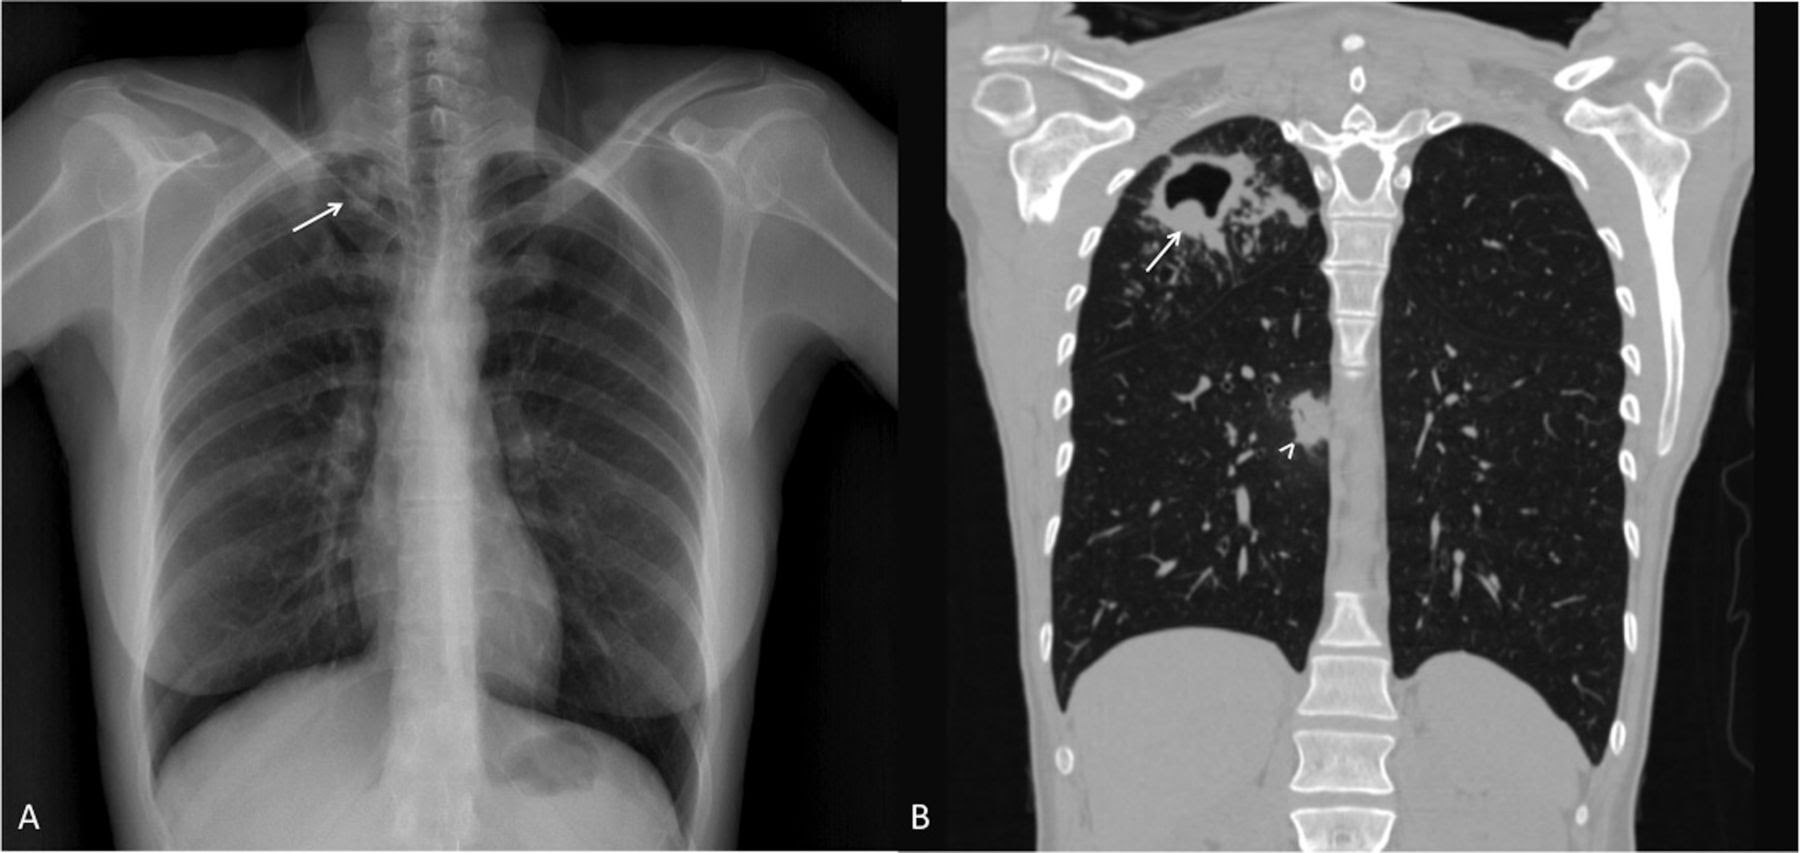

4.Рентгенограмма грудной клетки

Для выявления аномалий грудной клетки используется задне-передняя рентгенограмма грудной клетки. Поражения могут появиться в любом месте легких и могут отличаться по размеру, форме, плотности и кавитации. Эти отклонения могут указывать на ТБ, но не могут быть использованы для окончательной диагностики ТБ. Тем не менее, рентгенограмма грудной клетки может использоваться, чтобы исключить возможность легочного туберкулеза у человека, у которого была положительная реакция на ТКП или анализ крови на ТБ и не было симптомов заболевания.

Рентген грудной клетки при туберкулезе — Mobile Health

В некоторых случаях пациенту может потребоваться рентгенография грудной клетки при туберкулезе для подтверждения этого диагноза.

Что мне покажет рентген грудной клетки на туберкулез?

Рентген грудной клетки — это простая процедура для подтверждения наличия туберкулеза у пациента.

Во время процедуры врач сделает рентген грудной клетки под разными углами. Врач проанализирует результаты, чтобы определить, показывают ли рентгеновские снимки легких какие-либо признаки прогрессирующего туберкулеза легких. Врач также проверит наличие каких-либо повреждений у пациентов, у которых есть документально подтвержденные положительные результаты тестов.